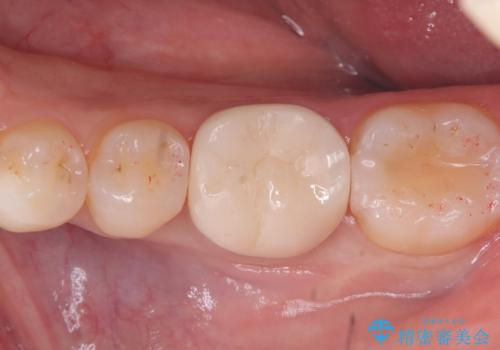

今後の破折リスクを説明し、セラミッククラウンでのやり替えとなりました。

頬舌的レジンインレーが入っており、歯質幅の薄かった且つ強く咬合していた遠心側歯質が欠けてしまっていました。また新しい窩洞のインレーを入れても、近心側歯質の破折のリスクは抱えたままになることから、クラウンでの修復をおすすめし審美性・適合性のよいセラミッククラウンでのやり替えとなりました。